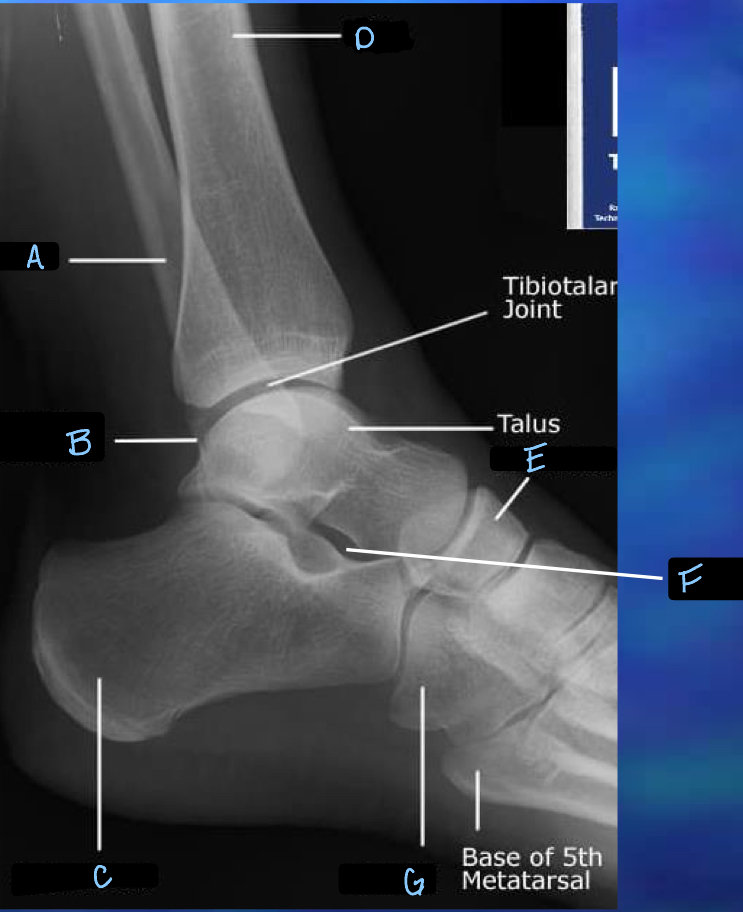

9

What is B?

lateral malleolus

10

What is C?

calcaneum

11

What is D?

tibia

12

What is E?

navicular

13

What is F?

sinus tarsi

14

What is G?

cuboid

What is A?

32

tibotalar joint

33

tarsals

34

metatarsals

35

phalanges

36

sesamoid bones

37

38

What is H?

39

What is I?

40

What is J?

fibula